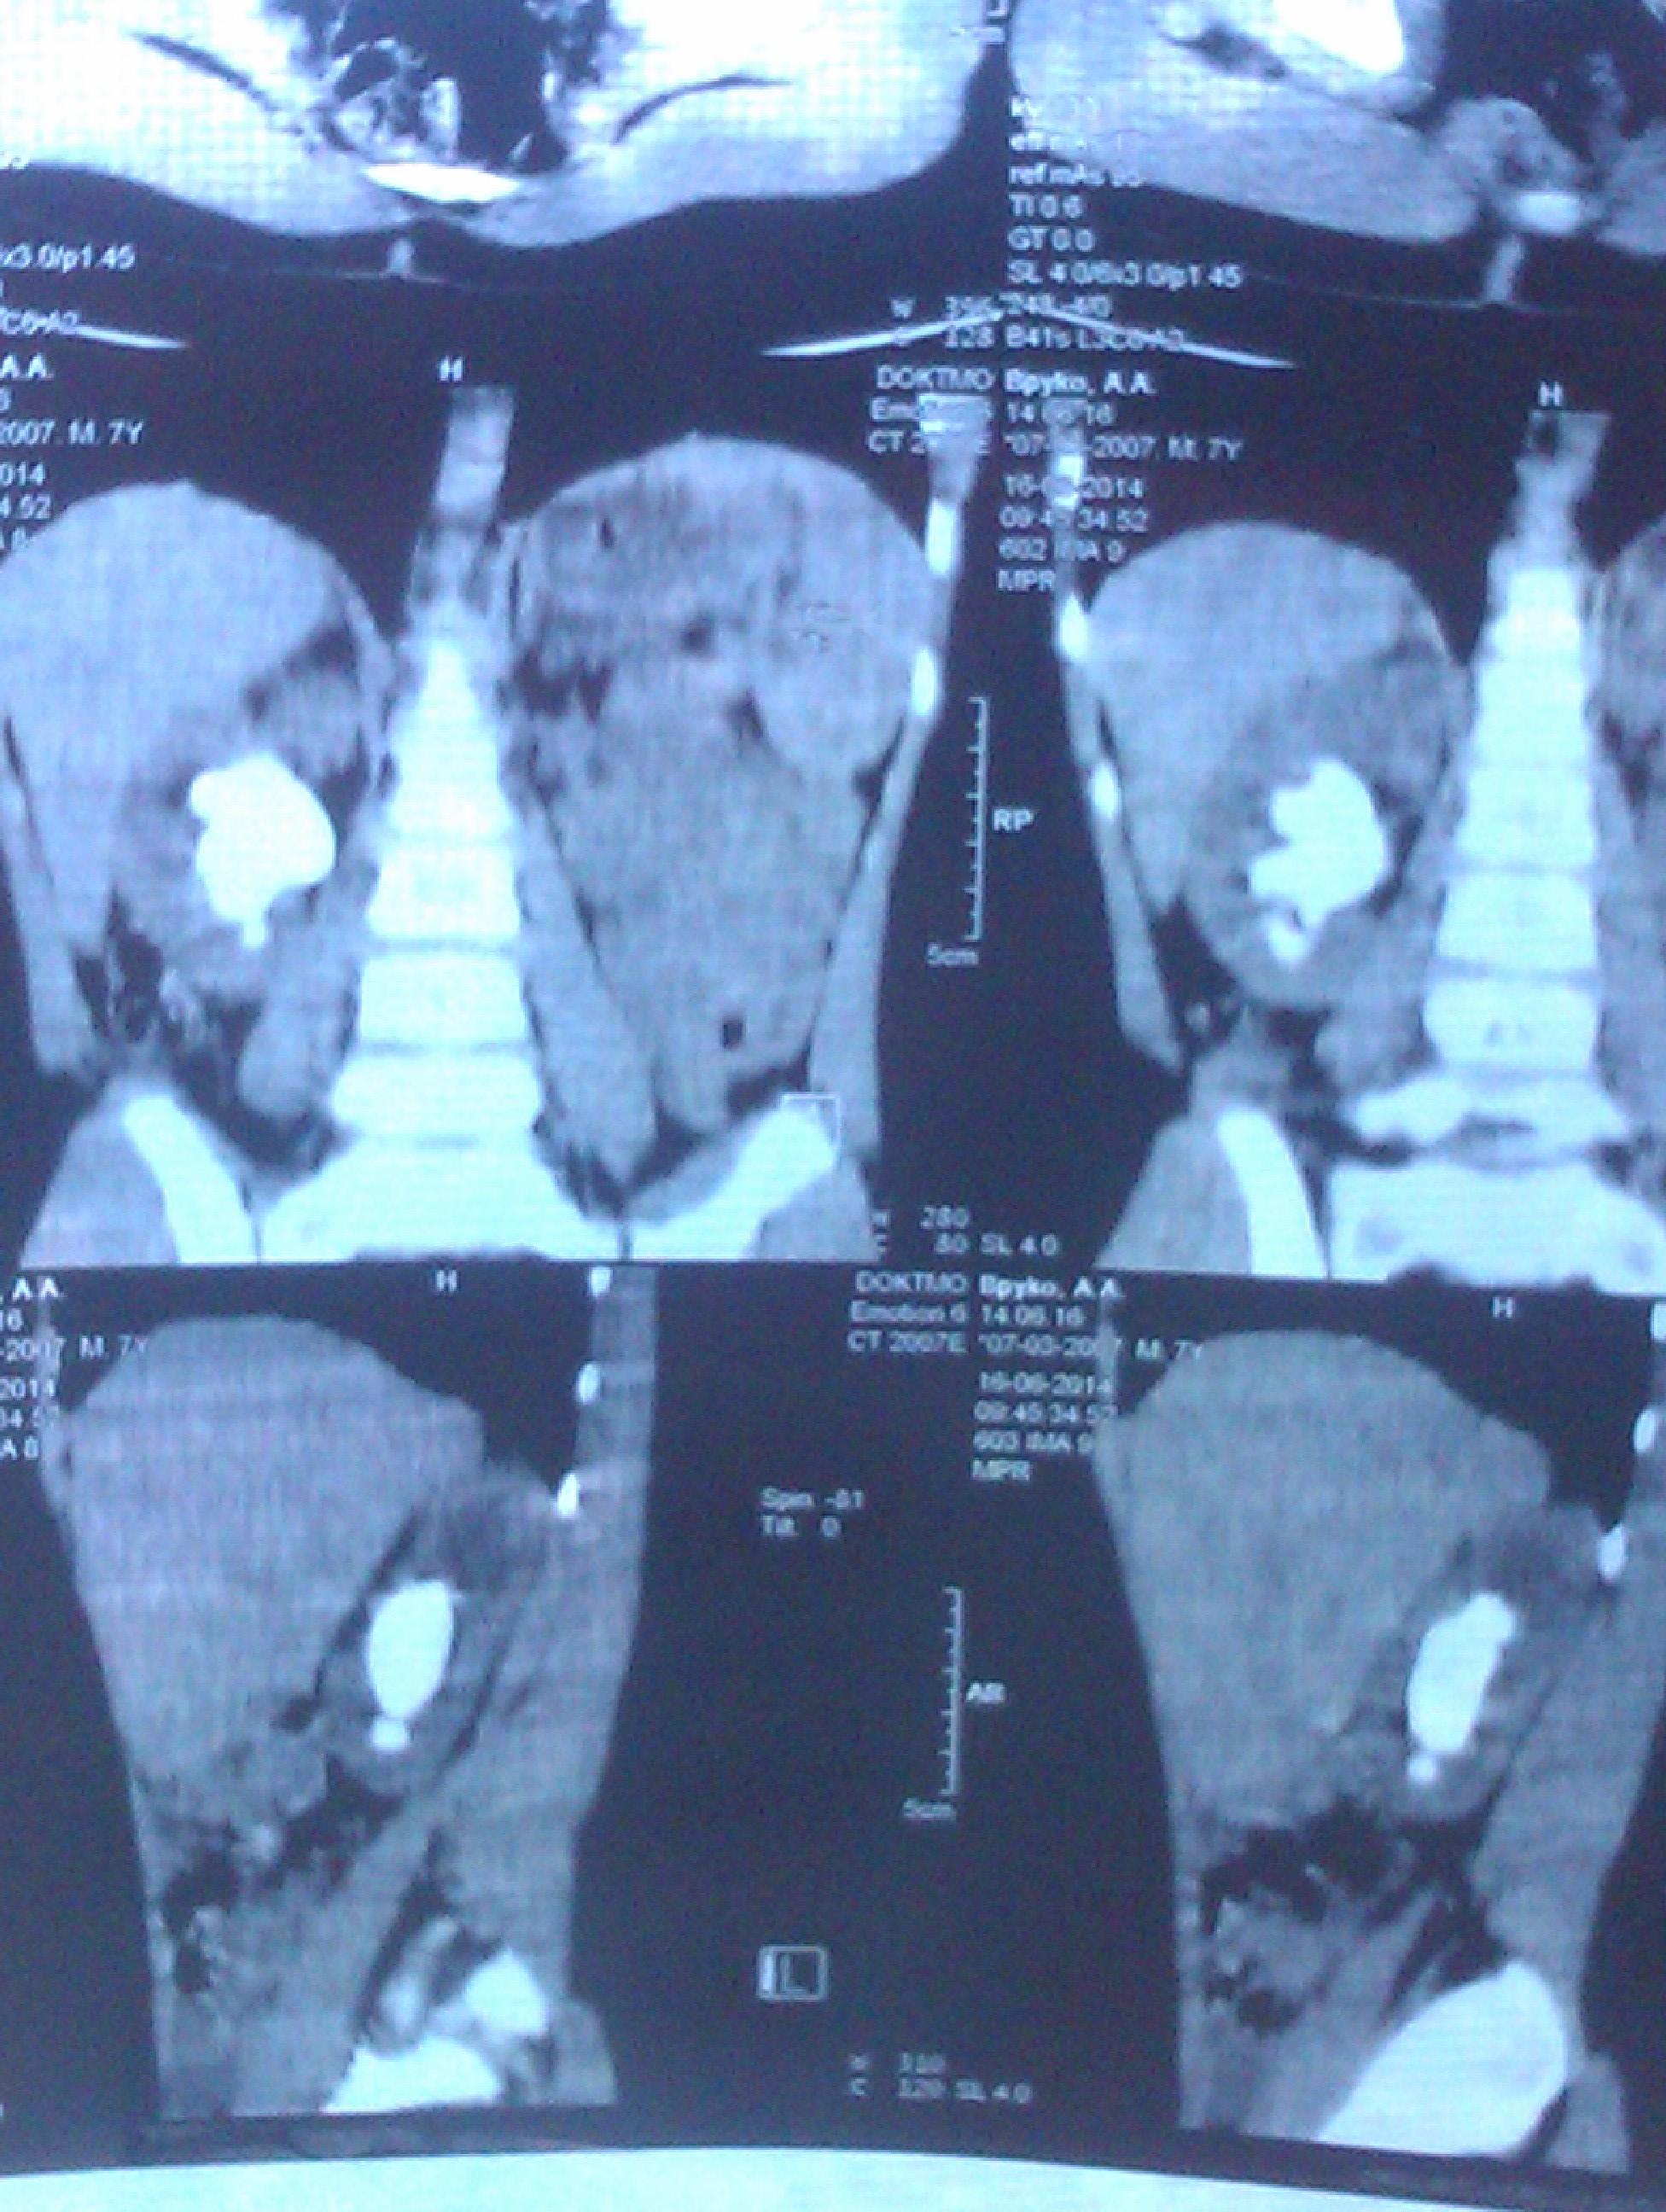

сыну 7.8 лет коралловый камень 3.5 х 4 .5 см в правой почке..в Украине таких операций детям до 14 лет не делают. возможно ли провести нефролапароскопию у вас в России и где именно.какова приблизительная стоимость оперпации.очень надеемся на Вашу любую помолщь..в Донецке идет война ,в Украину мы не поедем, в Европе очень дорого лечение. заранее благодарим за уделенное время . с ув.Бойко А. г.Донецк